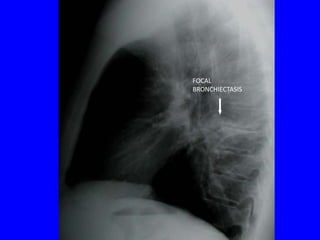

FOCAL BRONCHIECTASIS

Branching

tubular opacities

FOCAL

BRONCHIECTASIS

due to slow-growing

endobronchial tumour

Dilated bronchi

filled with mucus

tubular opacity

instead of air due to

proximal obstruction